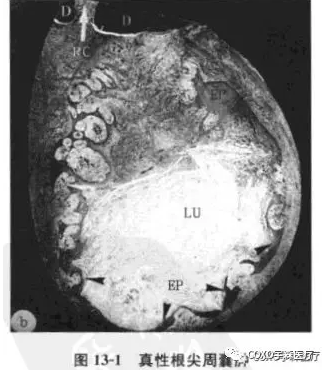

真性根尖周囊腫:包括4個(gè)主要成分:

①囊腔;

②囊壁上皮;

③上皮外組織;

④外周環(huán)形排列的膠原纖維。囊腔完全由上皮層包裹與根管隔離,腔內(nèi)一般含有壞死組織,偶爾含有膽固醇晶體。紅細(xì)胞和中性粒細(xì)胞主要存在于上皮層內(nèi)(圖13-1)